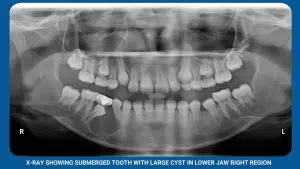

Sometimes, lesions go beyond diagnosis and require removal. Simple cysts, bumps, and infections? This is where lesion removal steps in, eliminating the troublesome tissue and promoting oral health.